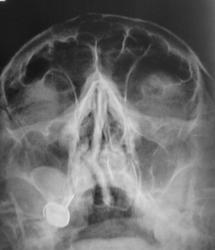

Пол пациента: Женский пол Тип патологии: Другое Область исследования: Челюстно-лицевая область и шея Методы исследования: Rg Пациент направлен отоларингологом на рентгенографии ППН. https://radiomed.ru/sites/default/files/styles/case_slider_image/public/user/12/2.pa130017.jpg?itok=v1ahIvCO https://radiomed.ru/sites/default/files/styles/case_slider_image/public/user/12/3.pa130018.jpg?itok=g_2UjqAl https://radiomed.ru/sites/default/files/styles/case_slider_image/public/user/12/4.pa130019a.jpg?itok=7_1J-Lyl ID:16132 Чт, 13/10/2011 - 20:10 #1 ДокRg Не на сайте Был на сайте: 12 лет 3 месяцев назад Зарегистрирован: 30.03.2011 - 20:05 Публикации: 105 Доброго времени суток уважаемые пользователи и гости сайта, моё мнение - одонтогенная киста правой в/ челюстной пазухи. Чт, 13/10/2011 - 20:16 #2 ДокRg Не на сайте Был на сайте: 12 лет 3 месяцев назад Зарегистрирован: 30.03.2011 - 20:05 Публикации: 105 и еще искривление носовой перегородки. Пт, 14/10/2011 - 18:48 #3 stovbav Не на сайте Был на сайте: 2 года 2 месяцев назад Зарегистрирован: 20.12.2009 - 17:28 Публикации: 7066 Согласен с коллегой...да и вспомнились высказывания на предмет не писать об искривлении перегородки...и как вот в ТАКОМ случае не написать? Болезни ног: виды, симптомы, причины, профилактика и лечение Пт, 14/10/2011 - 19:28 #4 Makcimalist Не на сайте Был на сайте: 11 лет 8 месяцев назад Зарегистрирован: 08.05.2010 - 14:28 Публикации: 1994 stovbav wrote: Согласен с коллегой...да и вспомнились высказывания на предмет не писать об искривлении перегородки...и как вот в ТАКОМ случае не написать? - Согласен! Считаю, нужно описывать такие отклонения от нормы! -------------- "Просто, по видимости, не видеть логики в очевидных вещах - это тоже одно из свойств некоторых умов, наряду с грустными думами о свойствах ума других." © Vega 08/10/2011 Пт, 14/10/2011 - 21:28 #5 Катенёв Валенти... Не на сайте Был на сайте: 7 лет 2 недели назад Зарегистрирован: 22.03.2008 - 22:15 Публикации: 54876 А, киста, прям - Венера Милосская!

Доброго времени суток уважаемые пользователи и гости сайта, моё мнение - одонтогенная киста правой в/ челюстной пазухи.

и еще искривление носовой перегородки.

А, киста, прям - Венера Милосская!